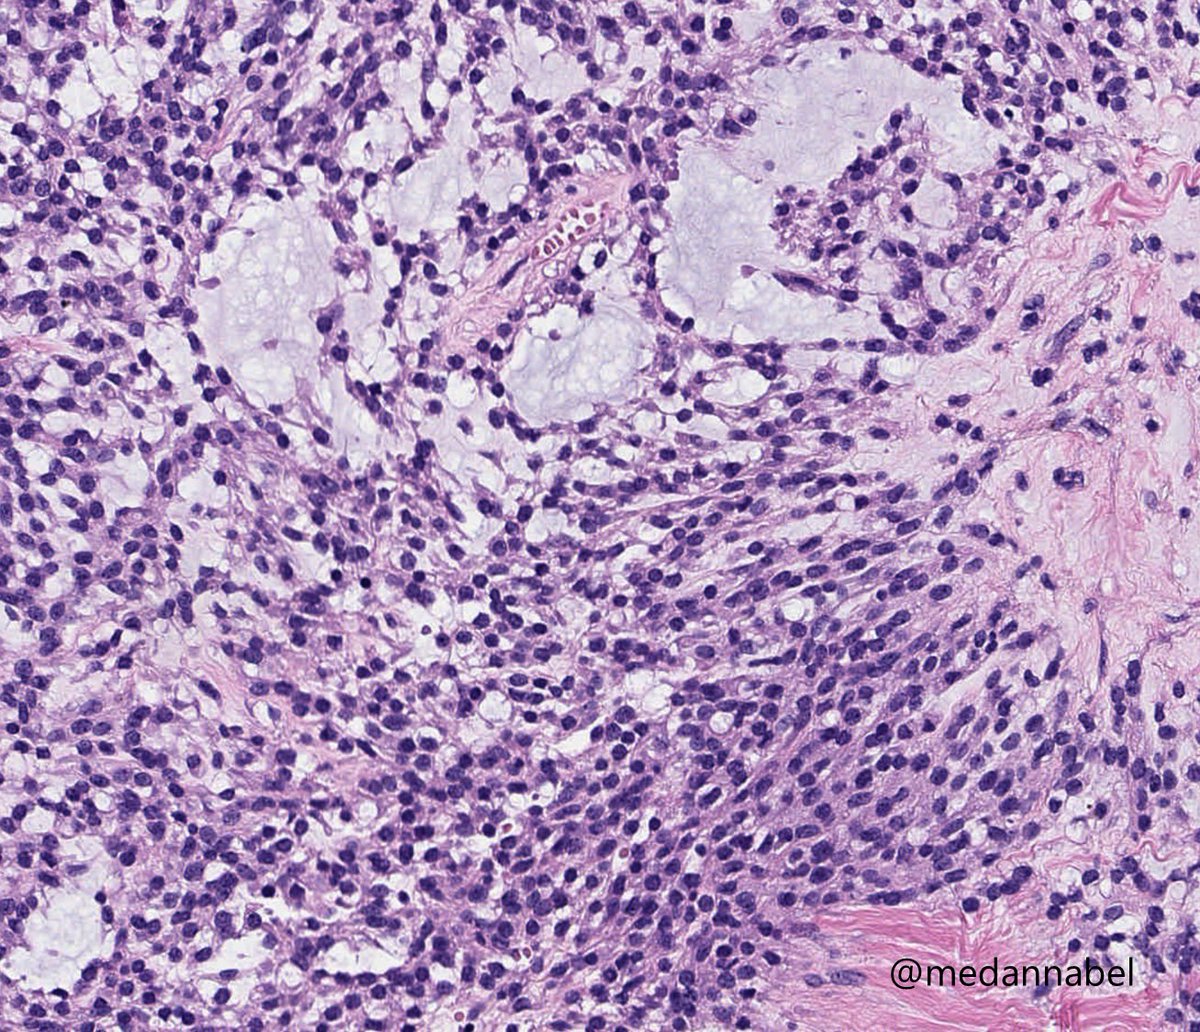

Pre-auricular nodule x 1month from 31yo patient, no other complaint. #pathtwitter #surgpath #ENTpath #hemepath #pathboards Einstein Montefiore Pathology Ridin Balakrishnan, MD Hansini Laharwani Siba El Hussein, MD Mitul B. Modi, MD Tristan Rutland MBBS FRCPA IFCAP Jerad Gardner, MD Kamran Mirza MD PhD - کامران مرزا